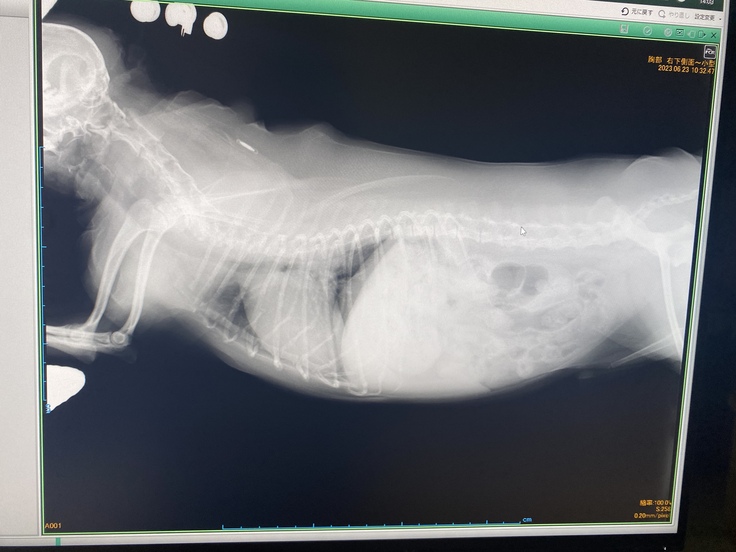

▼レントゲンの写真

恐れていた事態になってしまったとショックが隠しきれませんでした。

病状が進行していくと呼吸困難になることが何度もあり、入退院を繰り返しながら、苦しい状態と戦わなければいけない。

疲れていても横になって眠ることが出来ず、伏せの状態で気を失うように眠りにつく日々になるようです。